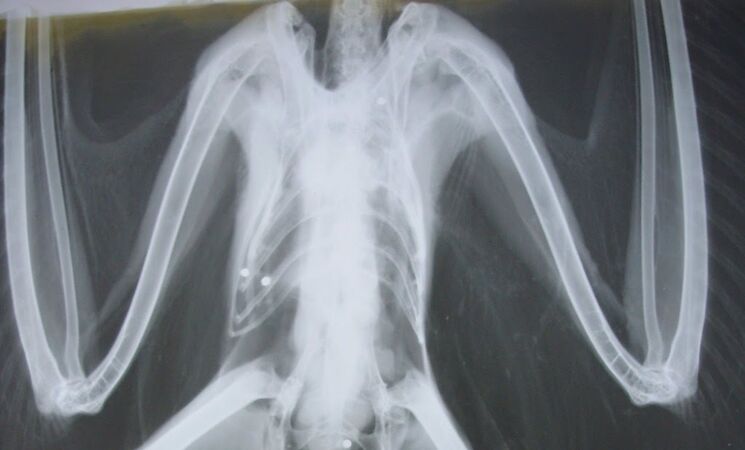

La organización SEO/BirdLife ha pedido al Gobierno y a las comunidades autónomas que velen por el cumplimiento de la prohibición de uso de munición de plomo en todos los humedales que ha entrado en vigor este 15 de febrero en el conjunto de los Veintisiete países de la UE y recuerda al Ejecutivo que tendrá que modificar la normativa para ajustarse a legislación europea.

En concreto, España era hasta ahora uno de los pocos países de los Veintisiete que prohibía su uso en humedales protegidos, pero según incide la ONG ahora deberá ampliar su prohibición a todas las zonas húmedas para salvar en torno a un millón de aves acuáticas al año en la UE.

La ONG calcula que entre 4.000 y 5.000 toneladas de plomo se vierten a la naturaleza la UE cada año y que estos perdigones son ingeridos comúnmente por aves acuáticas como cisnes, flamencos, patos y gansos, que las confunden con las piedrecillas que utilizan para facilitar la digestión de las duras semillas que comen.

En la actualidad, la Agencia Europea de Sustancias y Mezclas Químicas estima que anualmente esto genera la muerte por plumbismo de más de un millón de aves acuáticas.